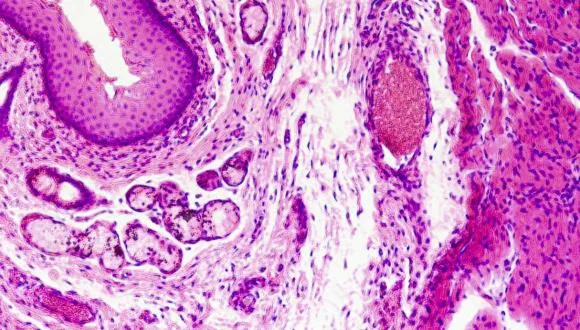

קבוצת חוקרים בינלאומית, בראשותו של פרופ' אלי שפרכר מהפקולטה לרפואה ע"ש סאקלר באוניברסיטת תל-אביב, מנהל מחלקת עור במרכז הרפואי תל-אביב, ופרופ' קטי גרין מאוניברסיטת נורטווסטרן בארה"ב, מדווחת בעיתון היוקרתי Nature Genetics, כי יחידות חלבוניות קטנות בשם דזמוזומים, המהוות חלק חשוב של המחסום העורי, משחקות תפקיד חיוני במניעת מחלות אלרגיות.

לאחרונה, חלה תפנית בהבנת הבסיס לתופעות אלרגיות. חוקרים רבים גורסים כעת כי ההפרעה בתפקוד מערכת החיסון במחלות אלה משנית לפגם ראשוני במבנה המחסום העורי. מחסום זה ממוקם בשכבות העליונות של העור ואחראי על שמירת מרכיבים חיוניים בעור, ומניעת כניסתם של גורמים חיצוניים מזיקים, כולל כאלה המסוגלים לעורר תגובה חיסונית לקויה. תוצאות המחקר מספקות כעת הוכחה חותכת לסברה זו, מה שצפוי להוביל לשינוי בגישה לפיתוח תרופות חדשות לתופעות אלרגיות.

ד"ר ליאת סמואלוב אשר הובילה יחד עם ד"ר עופר שריג את המחקר במרכז הרפואי תל-אביב, מציינת: "הדזמוזומים אחראים על הצמדת תאי העור זה לזה. מצאנו כי מרכיב חשוב של הדזמוזומים בשם דזמוגלאין 1 חסר בעורם של חולים הלוקים במחלה בשם תסמונת SAM, הבאה לידי ביטוי בתגובה עורית אלרגית קשה". שריג מוסיף: "המחלה נגרמת כתוצאה מהפרעה בבניית קשרים בין תאיים בשכבות העליונות של העור, מה שמאפשר לחלבונים שונים לחדור דרך העור ולעורר תגובה חיסונית מופרזת. המעניין אף יותר הוא שכשנבדקו במעבדה תאים שהופקו מעור החולים, נמצא שתאים אלה מפרישים עצמונית מגוון מתווכים של התגובה האלרגית. במובן זה, תוצאותינו מעלות שאלות לגבי תפקידה הראשוני של מערכת החיסון בגרימת אלרגיה, מה שכמובן צפוי להצביע על אסטרטגיות טיפוליות חדשות בדלקת עור אטופית ותופעות אלרגיות אחרות".